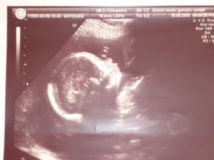

По фото 27 недели беременности врач определяет расположение малыша, состояние матки, сердцебиение ребенка, степень зрелости плаценты, параметры развития плода, количество и качество . . .

Нельзя назвать 27 неделю беременности для будущей матери простой, так как мучает усталость и мочеиспускание . Малыш активно набирает в весе и развивается . Статья содержит фото с УЗИ .

27 -я акушерская неделя соответствует примерно 25-й эмбриональной, и значит вы беременны уже без одной недели 7 месяцев . Маленький человечек уже имеет 85%-ный шанс выжить, если роды случаться . . .